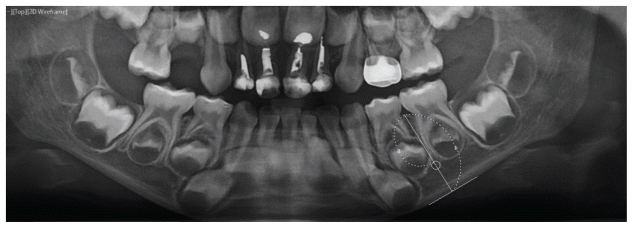

The horizontal positioning of the MF was established using the digital ruler tool (7), in accordance with the classification proposed by Chkoura and El-Wady (6). The position of the MF relative to the premolars was categorized as follows (see Figure 1):

- Type 1: Mesial to the apex of the first premolar.

- Type 2: In line with the apex of the first premolar.

- Type 3: Between the apices of the first and second premolars.

- Type 4: In line with the apex of the second premolar.

- Type 5: Between the apices of the second premolar and the first molar.

For measurements involving primary molars, tangential lines were delineated on the mesial surface of both the first and second primary molars, along with lines extending from the central region of the crowns through the area situated between the two roots. It is noteworthy that primary molars generally have two roots, (6). The classification for the MF associated with primary molars was subsequently articulated as follows:

- Type 1m: Mesial root of tooth D.

- Type 2m: Apex of tooth D.

- Type 3m: Distal root of tooth D.

- Type 4m: Between teeth D and E.

- Type 5m: Mesial root of tooth E.

- Type 6m: Apex of tooth E.

- Type 7m: Distal root of tooth E.